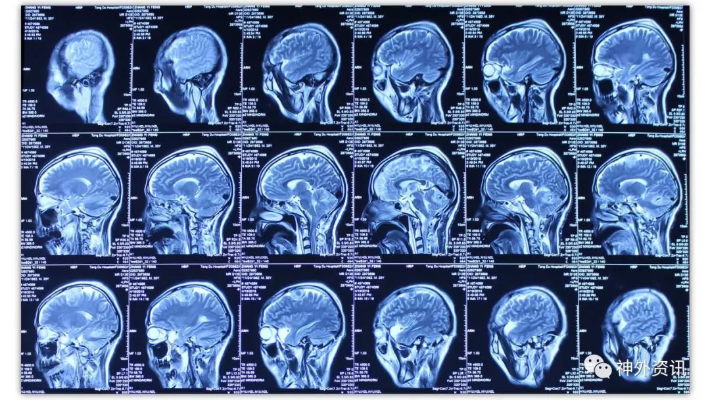

经乙状窦后联合远外侧入路切除岩斜-枕骨大孔-颈2脑膜瘤一例